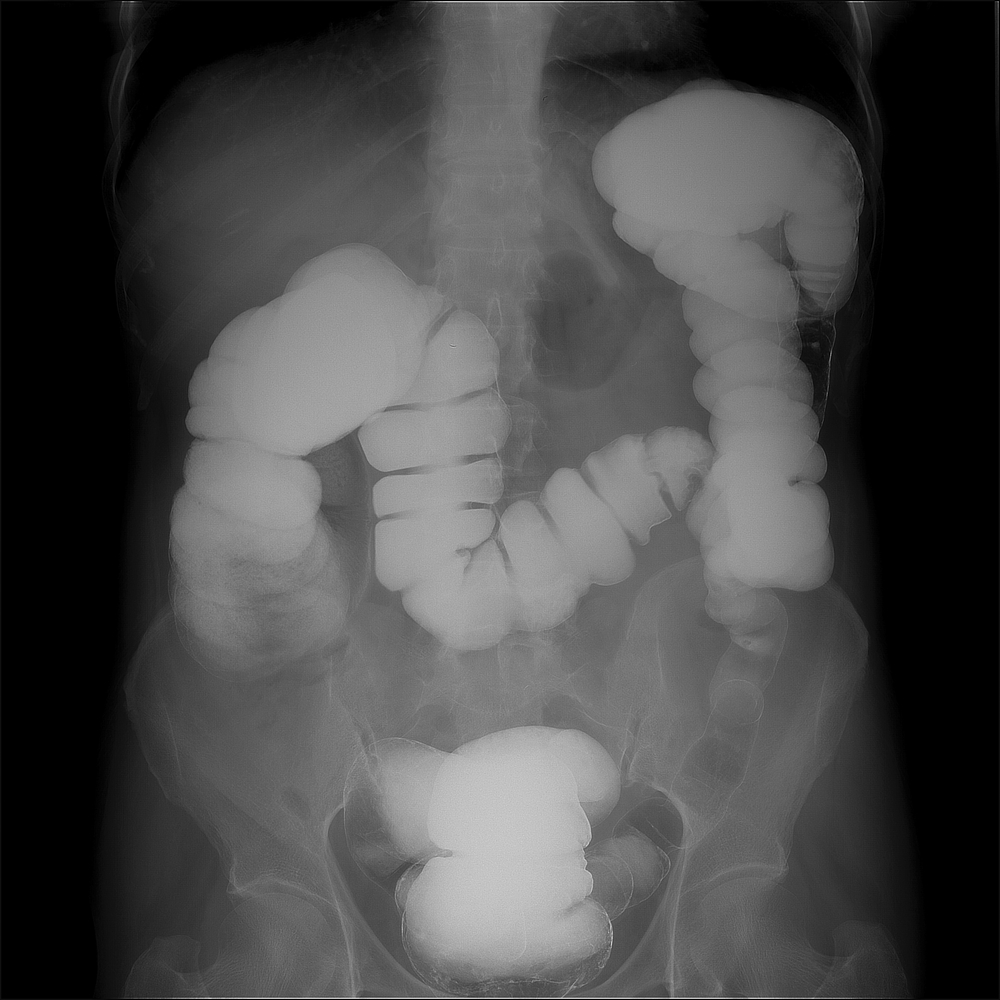

Barium enemas

A barium enema is a procedure in which barium sulfate, a radiopaque contrast agent, is introduced into the rectum and colon via the anus. The barium sulfate coats the lining of the gastrointestinal tract and makes it visible on X-ray or fluoroscopic examination.

Barium enemas help doctors evaluate conditions such as intestinal obstruction, inflammation, or malignant tumors. They may also detect abnormal contours or areas of bleeding in the intestine.

A radiologist or gastroenterologist typically performs the procedure. A nurse or technologist will insert a flexible tube (catheter) into the patient’s anus and slowly inject the barium sulfate solution into the rectum and colon. The patient may need to change positions during the procedure to help distribute the barium evenly.

Once the barium has coated the intestine, the technician will take the X-ray or fluoroscopic images. These images will help medical professionals evaluate the structure and function of the intestine.